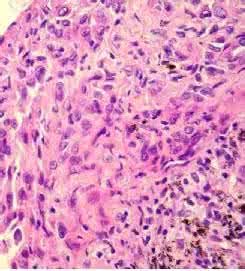

感染性肉芽腫引起機體免疫反應,特別是細胞免疫反應,使巨噬細胞轉變成上皮樣細胞和多核巨細胞。上皮樣細胞鏡下細胞質呈粉紅色,略呈顆粒狀,細胞質界限不清,細胞核呈圓形或長圓形,有時核膜摺疊,染色淺淡,核內有1~2個核仁。

上皮樣細胞